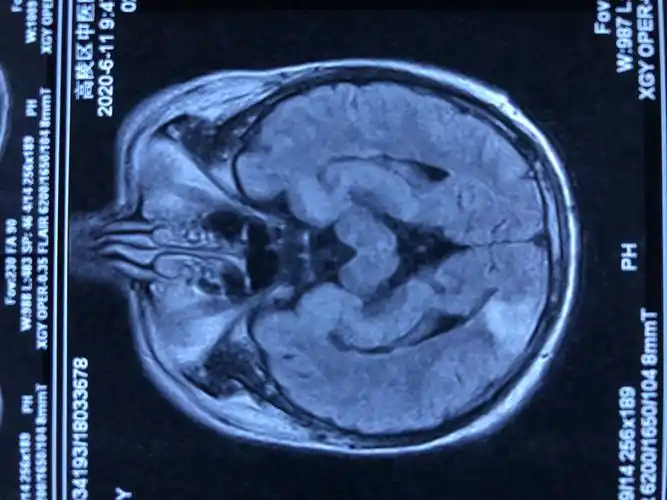

头部磁共振图像

请医生看看头颅磁共振片子

脑部核磁共振光片图